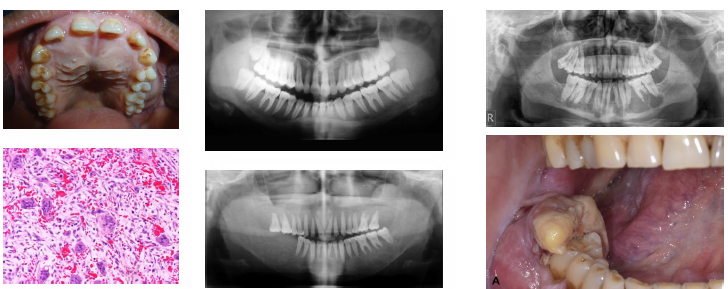

oral squamous cell carcinoma overview

•Most common Malignant tumor of oral stratified epithelium

•Strongly linked to tobacco and alcohol use

•HPV-related cases occur in oropharynx

•Often arises from premalignant lesions

•Includes several aggressive histologic variants

oral squamous cell carcinoma clinical features

•Non-healing ulcer or exophytic mass lesion

•Mixed red and white mucosal appearance

•Induration on palpation is key finding

•Common on tongue and floor of mouth

•May be painless early and painful later

Verrucous carcinoma overview

•Low-grade variant of squamous cell carcinoma

•Strongly associated with tobacco use

•Slow-growing but locally invasive lesion

•Rarely metastasizes to distant sites

•Often arises from leukoplakic lesions

verrucous carcinoma clinical features

•Thick white verrucous or papillary mass lesion

•Broad-based lesion with slow enlargement

•Often involves buccal mucosa or gingiva

•Surface appears rough and warty (verrucous)

•Typically painless in early stages